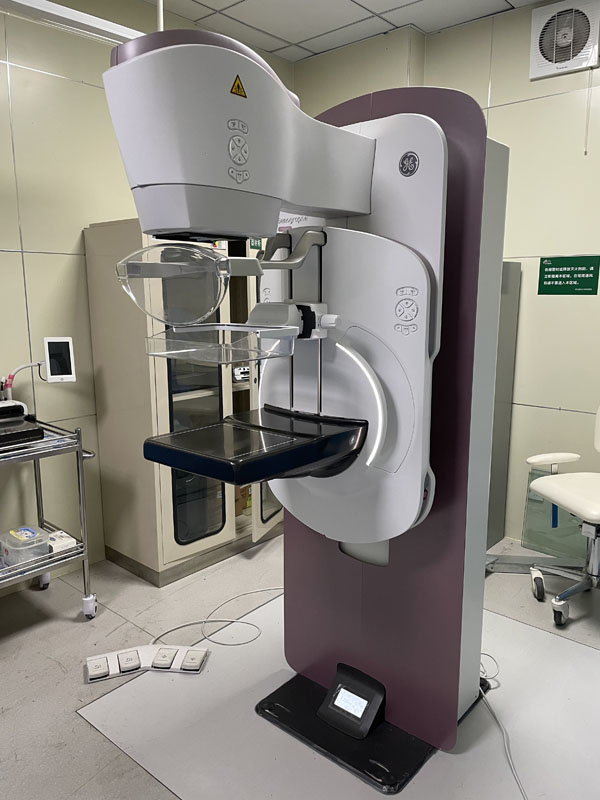

国内首台具有数字乳腺断层摄影(DBT)和CEM引导下穿刺功能的X线机